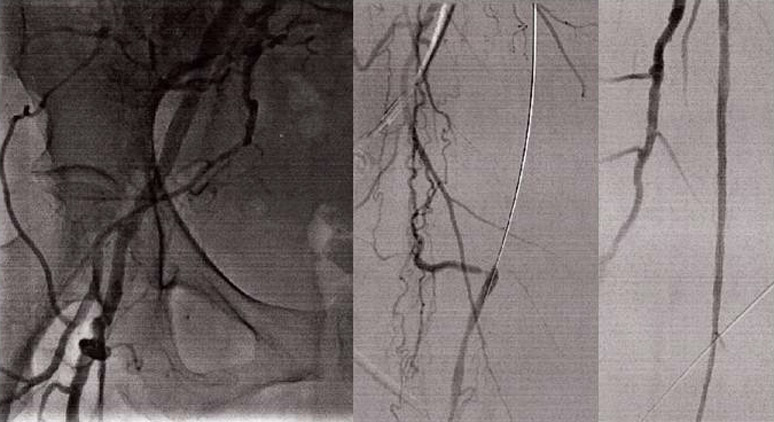

GENDER: Male

AGE: 57 years old

DEVICE: Wingman™

PHYSICIAN: Peter A. Soukas, MD, FACC, FSVM, FSCAI, FACP, RPVI

• Smoker with high blood pressure, hyperlipidemia, moderate CAD; by cath, presents with severe right calf claudication that has progressed to occasional nocturnal rest pain

• Seen by local vascular surgeon who performed angiography confirming right popliteal occlusion

• Fem-tib bypass recommended; came for a second opinion

• Successful Wingman™-assisted antegrade AT access

• Laser Pop/AT, PT wire crossing, laser TPT/PT

• IVL, balloon, drug-eluting stent and DCB

• Successful 3-vessel runoff on what was previously completely occluded